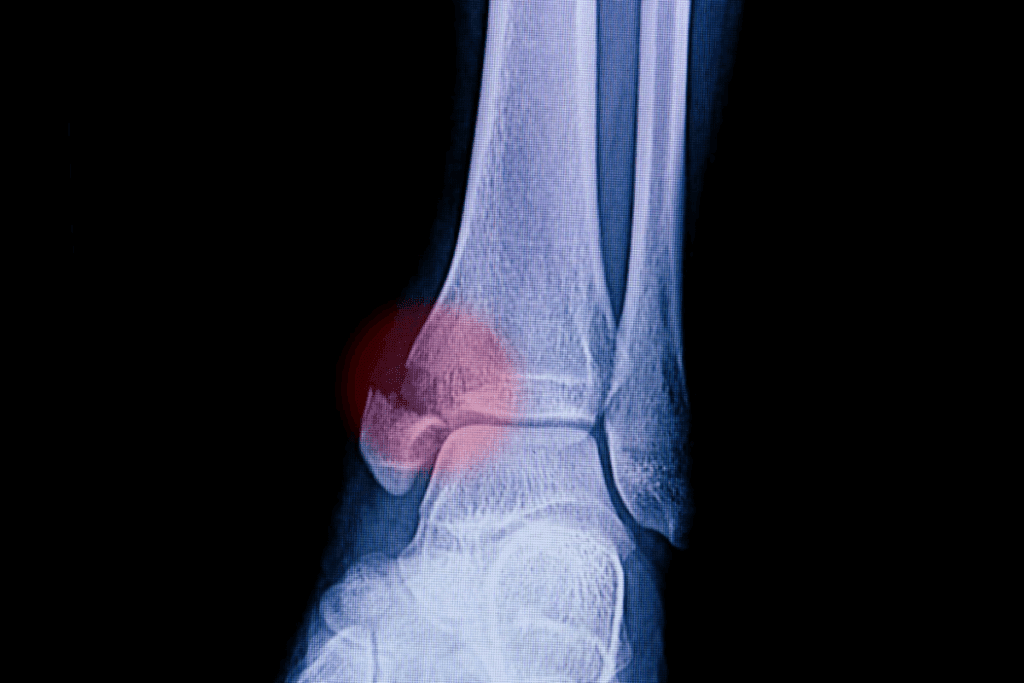

Advanced imaging guides our decisions. CT scans reveal hidden cracks, while X-rays confirm alignment after manual adjustments. Missed fractures risk improper healing, leading to chronic pain or arthritis.

X-rays remain our first-line tool, detecting 92% of bone displacements. For complex cases involving cartilage damage, CT scans map fracture lines in 0.5mm detail. When ligament evaluation becomes critical, MRI reveals soft tissue tears invisible to other methods.

Accurate diagnosis prevents misaligned healing – a key factor in preserving long-term mobility. Our radiologists work alongside orthopedic specialists to interpret results within 90 minutes of imaging completion.